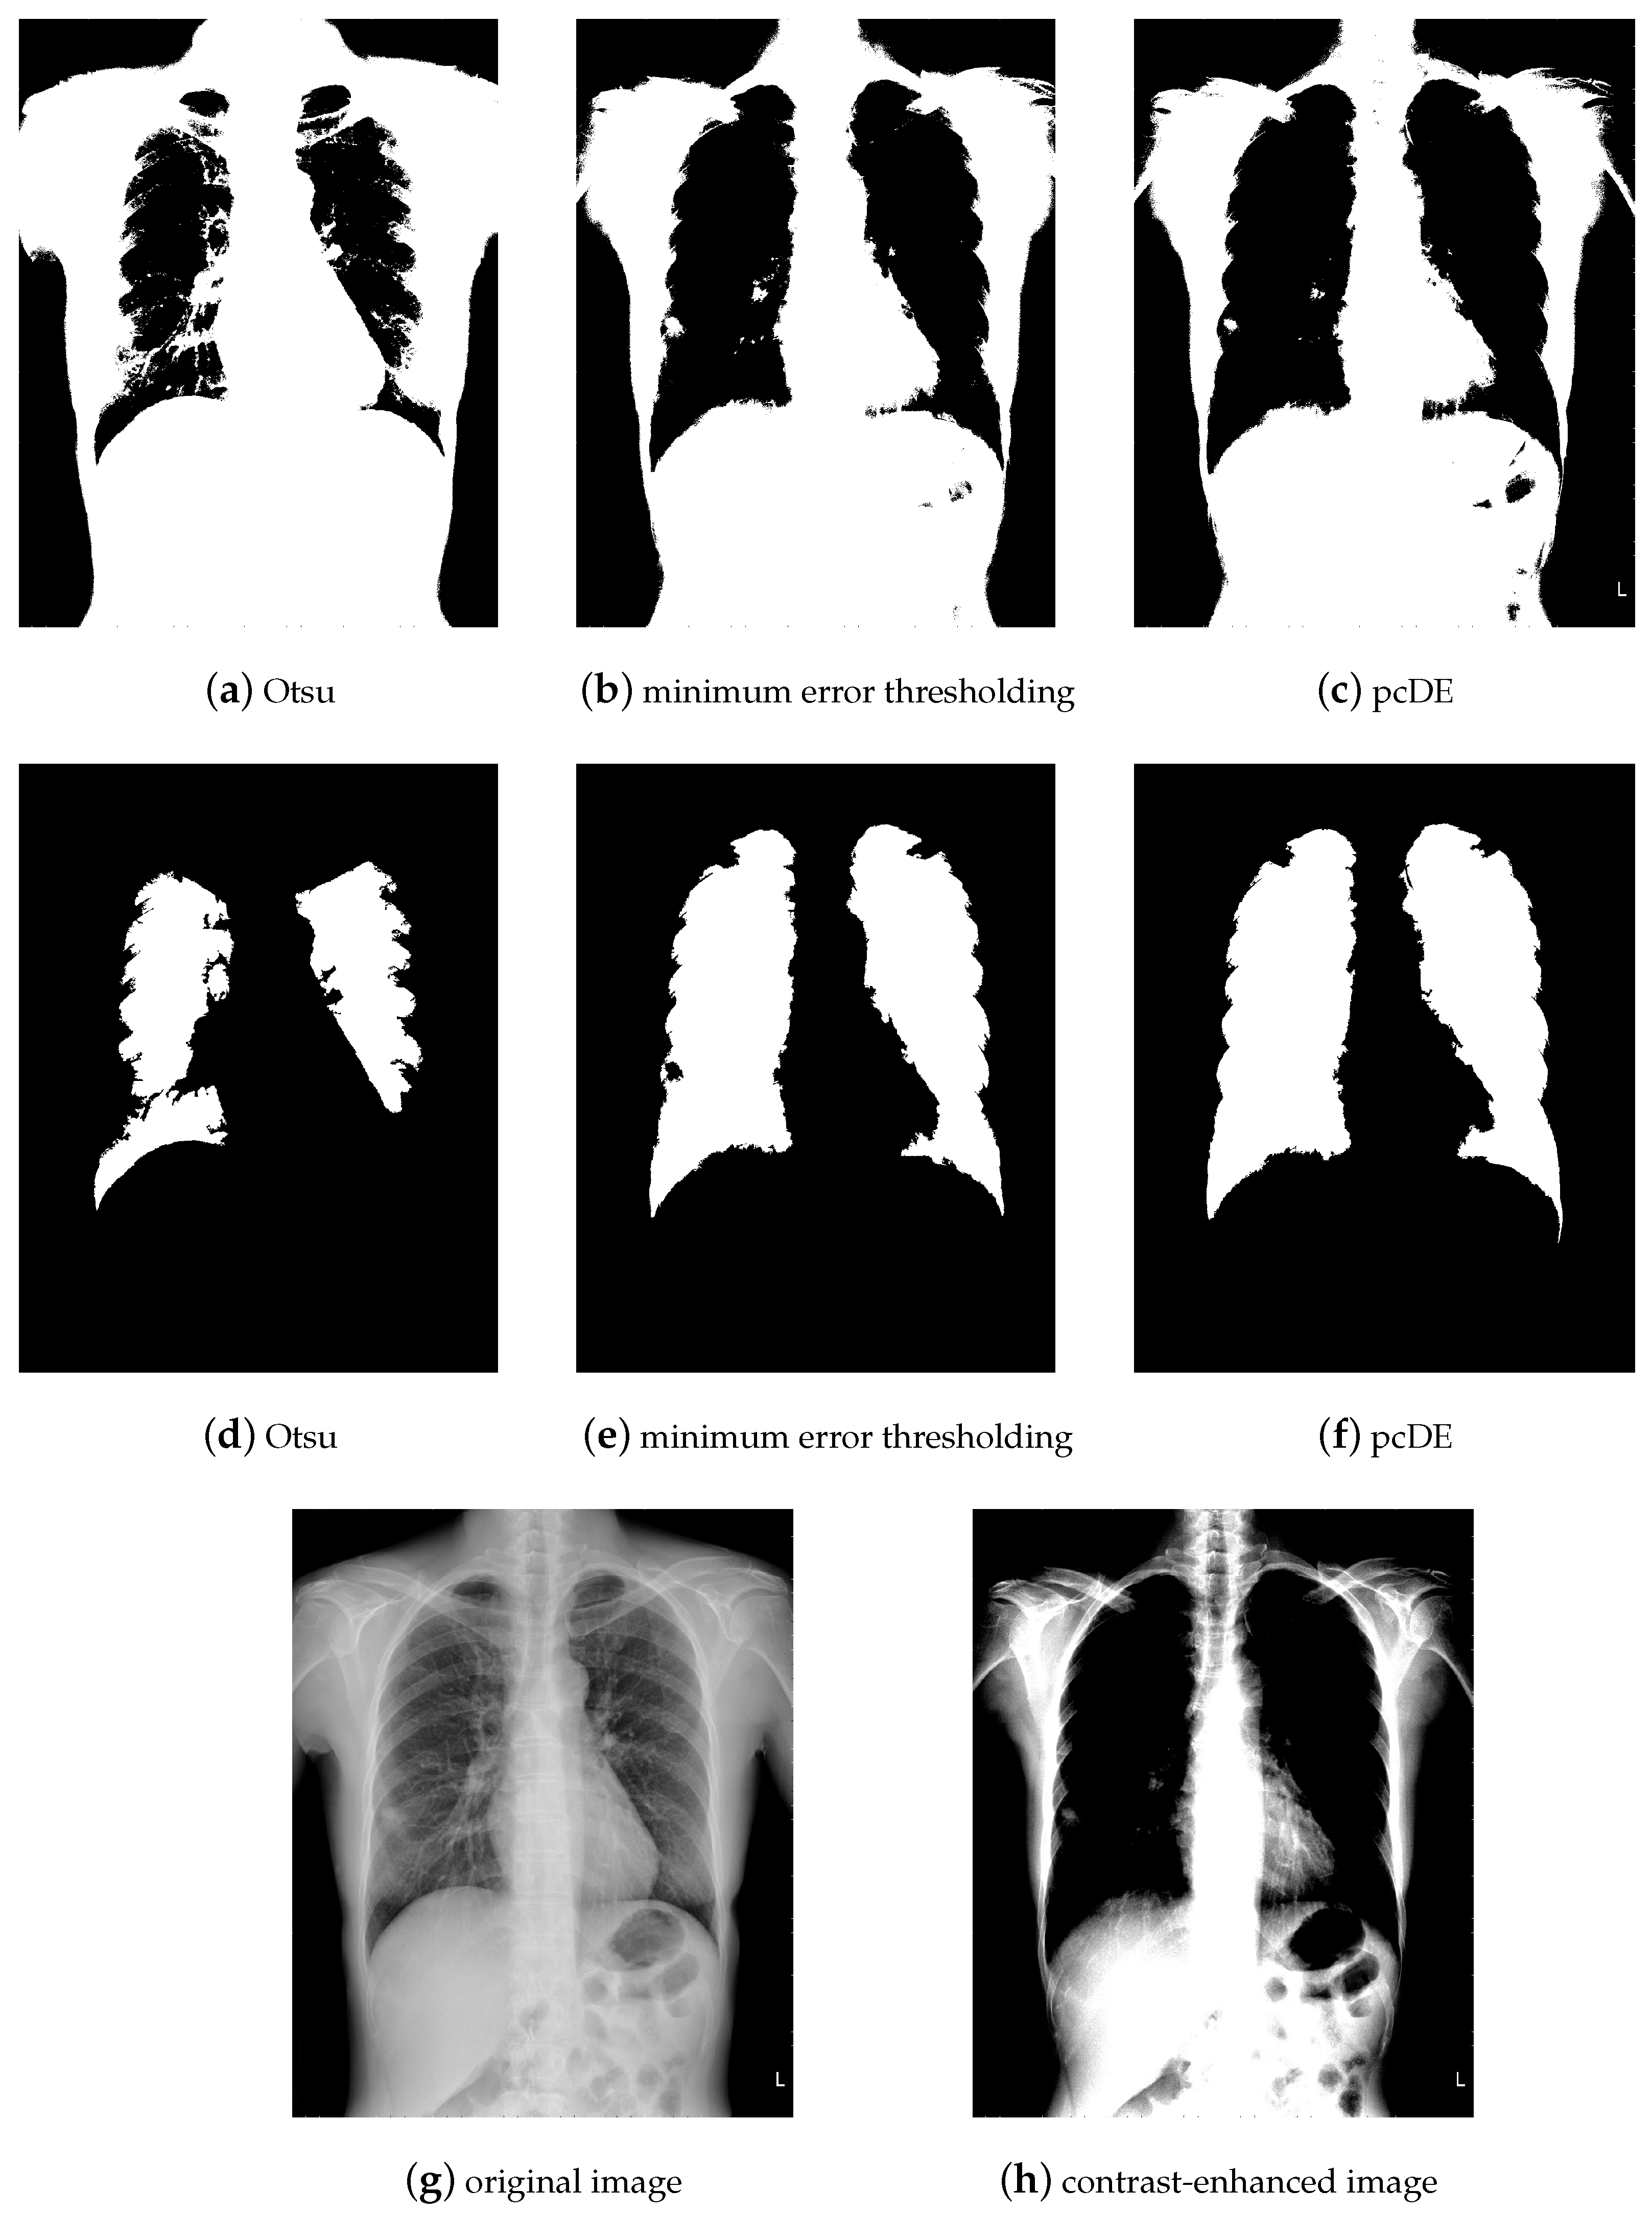

5. Case of Study: Parallel Compact Differential Evolution for Image Segmentation

- Image preprocessing. Enhance the contrast of the image to achieve better segmentation.

- Calculate the optimal threshold for image segmentation through different methods to get the binarized image.

- Use morphological methods to process images to extract targets.

- Mark target contour.

- : Represent the result of ground truth segmentation (Figure 13).

- : Represent the result of algorithm segmentation.

| Segmentation Method | Original Image | Noisy Image |

|---|---|---|

| Otsu | 0.9210 | 0.9531 |

| minimum error thresholding | 0.9732 | 0.9093 |

| pcDE | 0.9738 | 0.9684 |